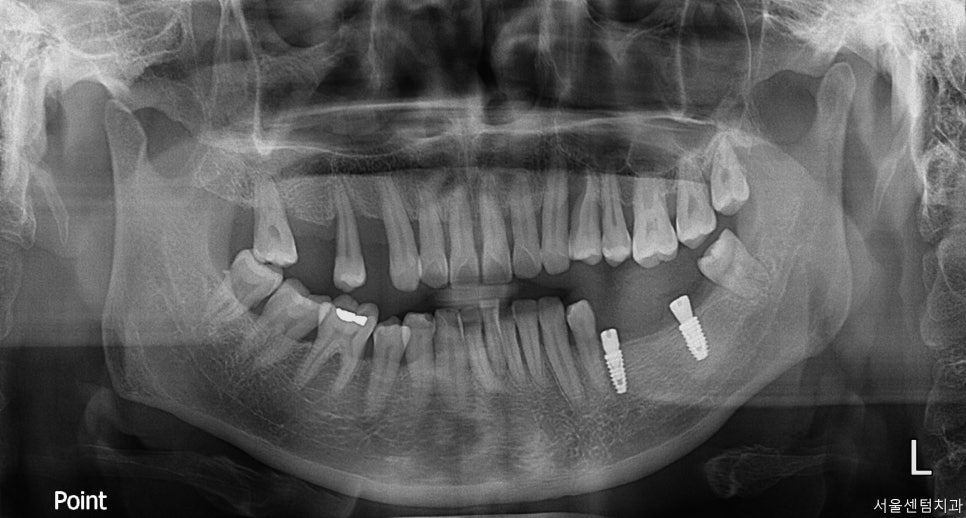

먼저 하악의 임플란트 먼저 식립을 진행하였는데요.

처음 방문하신 이후 약 10일 후에 진행하였습니다.

그 이후 상악은 한 달 뒤쯤 식립하였습니다.

상황에 따라 위에를 먼저 할지 아래를 먼저 할지

보기도 하는데 이분 같은 경우 양쪽 다

치아가 없으시다 보니 한쪽이라도 먼저

식사하실 수 있게 비교적 보철이 빨리 올라갈 수 있는

하악 어금니 수술을 먼저 진행하였습니다.